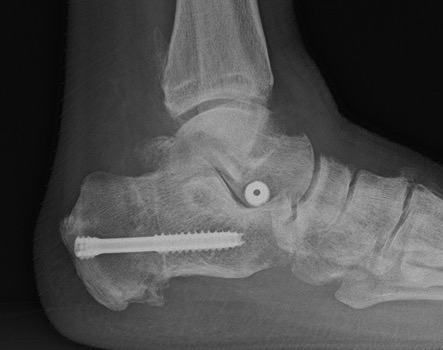

Medial displacement calcaneal osteotomy

Technique

Lateral approach

- curve just below peroneals

- protect sural nerve branches

- homann superiorly in front of tendoachilles

- homann inferiorly under calcaneum

Oblique osteotomy behind posterior facet

- 45o cut with saw

- open with lamina spreader

- split periosteum medially with osteotome

- avoid damage to medial structures

- transfer medially 1 cm

- screw fixation